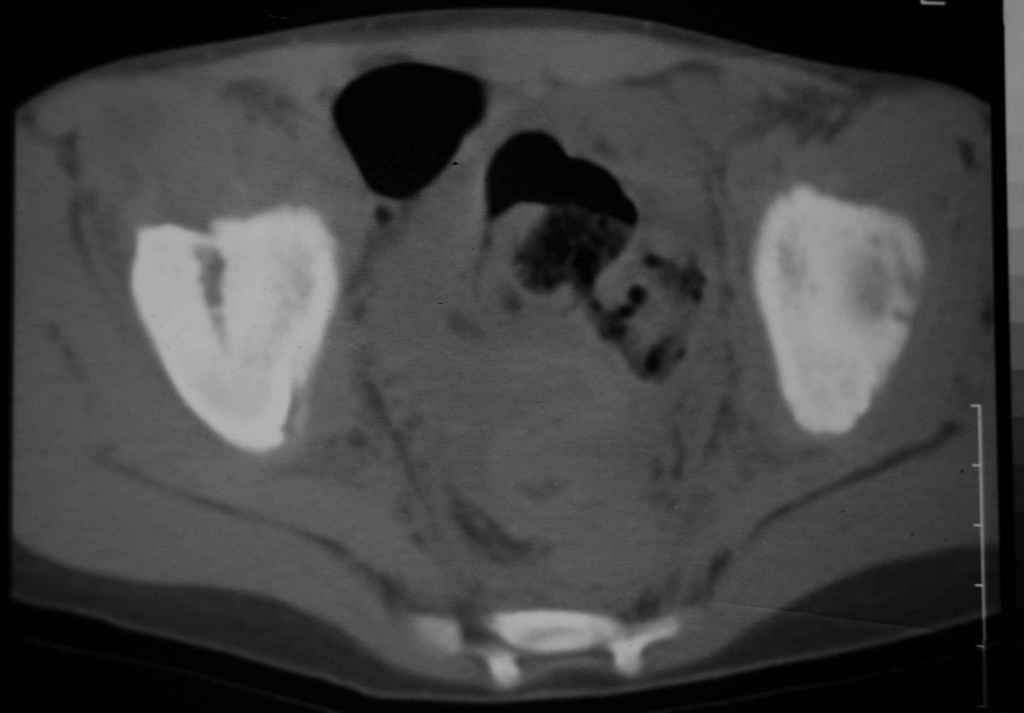

Уважаемые коллеги, помогите определиться с тактикой лечения.Ребёнок 7 лет, травма 11.09.08, поступил с травматическим вывихом бедренной кости.

Вывих вправлен, конечность фиксирована на скелетном вытяжении. Что делать с переломом подвздошной кости? Лечить консерватино или оперировать?

Уважаемый Алексей! Операция не требуется. Продолжить ск вытяжение.

Можете спокойно продолжать консервативное лечение.